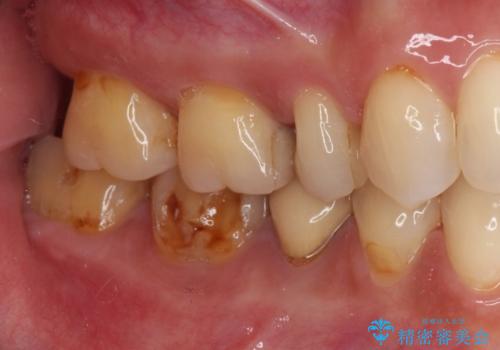

奥歯が欠けてしまった オールセラミッククラウンによる補綴治療

- 奥歯が欠けてしまった事を主訴として来院した患者様です。

頬側の欠けている範囲が大きく、以前治療した詰め物も大きいため、詰め物を外してむし歯を除去し、

形を整えて一度仮歯に置き換え、フルジルコニアクラウンにて補綴しました。

高強度のフルジルコニアクラウンは、強いかみ合わせでも壊れにくいです。

また審美的にも満足していただけました。